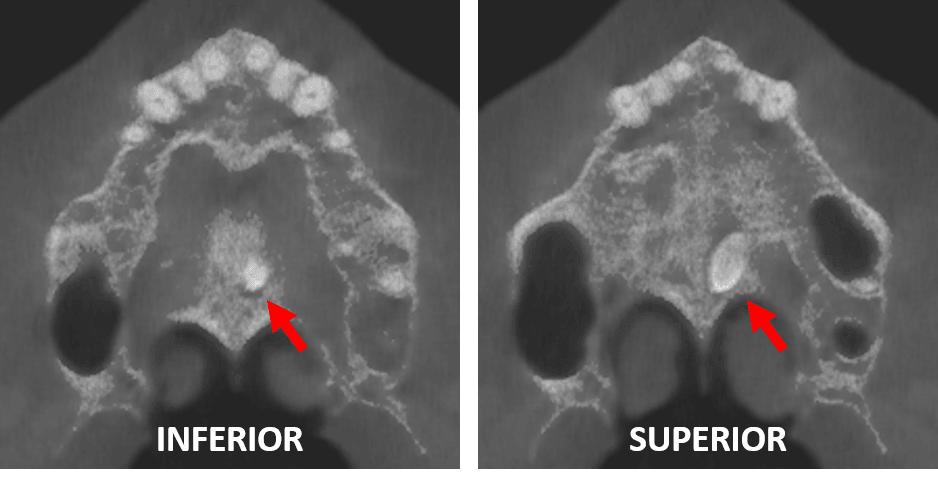

Fig.4

En la representación tridimensional (Fig.4) en proyección de máxima intensidad, se observa la densidad dentaria antes mencionada, tratándose de un diente supernumerario compatible con Mesiodens.

Los dientes supernumerarios o hiperdoncia pueden definirse como dientes que exceden la dentición normal, independientemente de su ubicación y morfología Es más frecuente en la región central del maxilar superior o inferior; sin embargo, su aparición en la mandíbula es poco frecuente. El mesiodens es el tipo más común de diente supernumerario y se localiza en la línea media entre los dos incisivos centrales superiores. Su prevalencia en la población general oscila entre el 0,15 % y el 1,9 %, y se ha descrito que es más frecuente en hombres que en mujeres. Se ha estimado que la frecuencia del mesiodens es del 0,45 % en la población caucásica, del 0,4 % en la finlandesa, del 1,43 % en la noruega y del 2,2 % en la hispana. Las variaciones debidas a diferencias en las susceptibilidades demográficas y ambientales pueden influir en la prevalencia descrita. Los dientes supernumerarios se clasifican según su morfología (cónicos, tuberculados y suplementarios), la localización (mesiodens, paramolar, distomolar y parapremolar), la posición (vestibular, palatal y transversal) y la orientación (vertical o normal, invertida, transversal u horizontal). En el presente caso, se trataba de un mesiodens cónico, palatal e invertido. La aparición de un mesiodens es muy poco frecuente en la región palatina media. Es probable que debido a la fuerza de erupción del incisivo central, el diente podría haberse desplazado hacia la región palatina media.